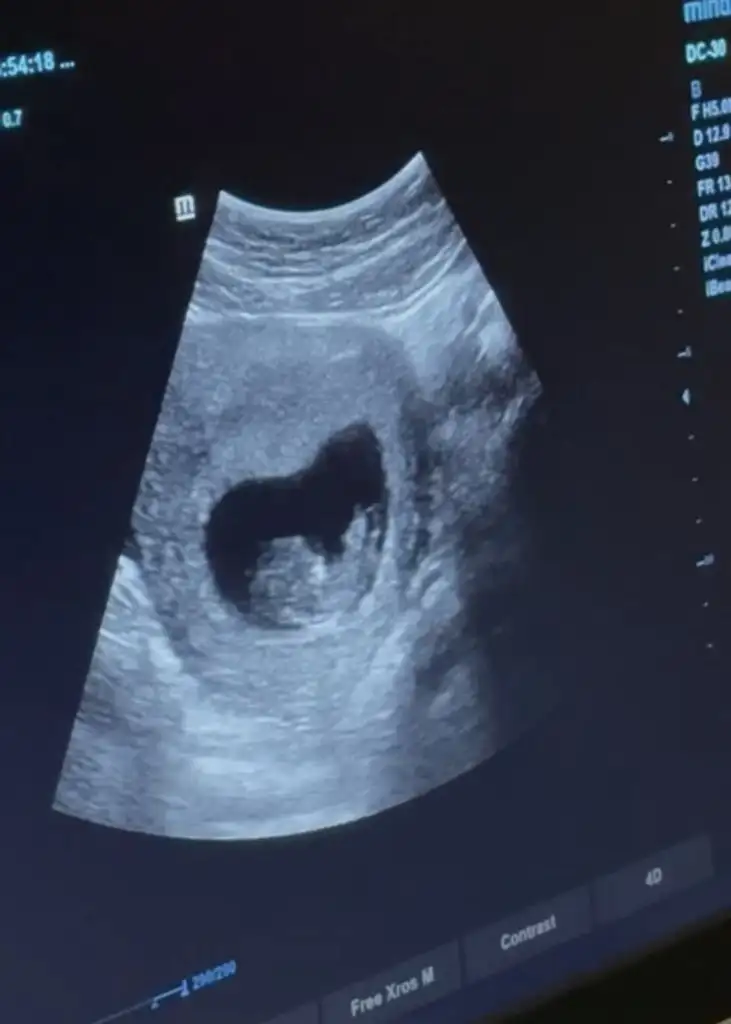

Banana bakarmisiniz

Kızlar bı arkadaş keseye göre tahmin yapıyor ve hep tutuyormuş iki oğlunu da bu şekilde cok yeniyken bile tahmin etmiş...ogullarinda kesesi hep uzunmuş muz gibi...yuvarlak ve yuvarlağa yakın olanlar hep kızdır diyor..ve bayağı emin konusuyor..benimki şişman bı fasulye gibi oo kesin kız görürsün dedi...sizlerin keselerinin şekli nasıldı ve cinsiyet neydi konusalimmi 😊